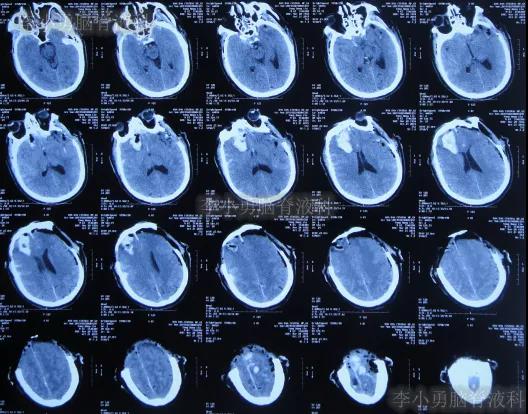

继续治疗1周时间内,曾3次复查头颅CT(图-5、图-6、图-7)均示脑膨出逐渐加重的趋势,仍有积血;期间给予腰大池引流。

图-5:2019年10月26日头颅CT

图-6:2019年10月29日头颅CT

图-7:2019年10月31日头颅CT

图-8:2019年11月3日头颅CT

开颅术后18天即2019年11月7日,脑膨出进一步好转(图-9)。

图-9:2019年11月7日头颅CT

图-10:2019年11月15日头颅CT